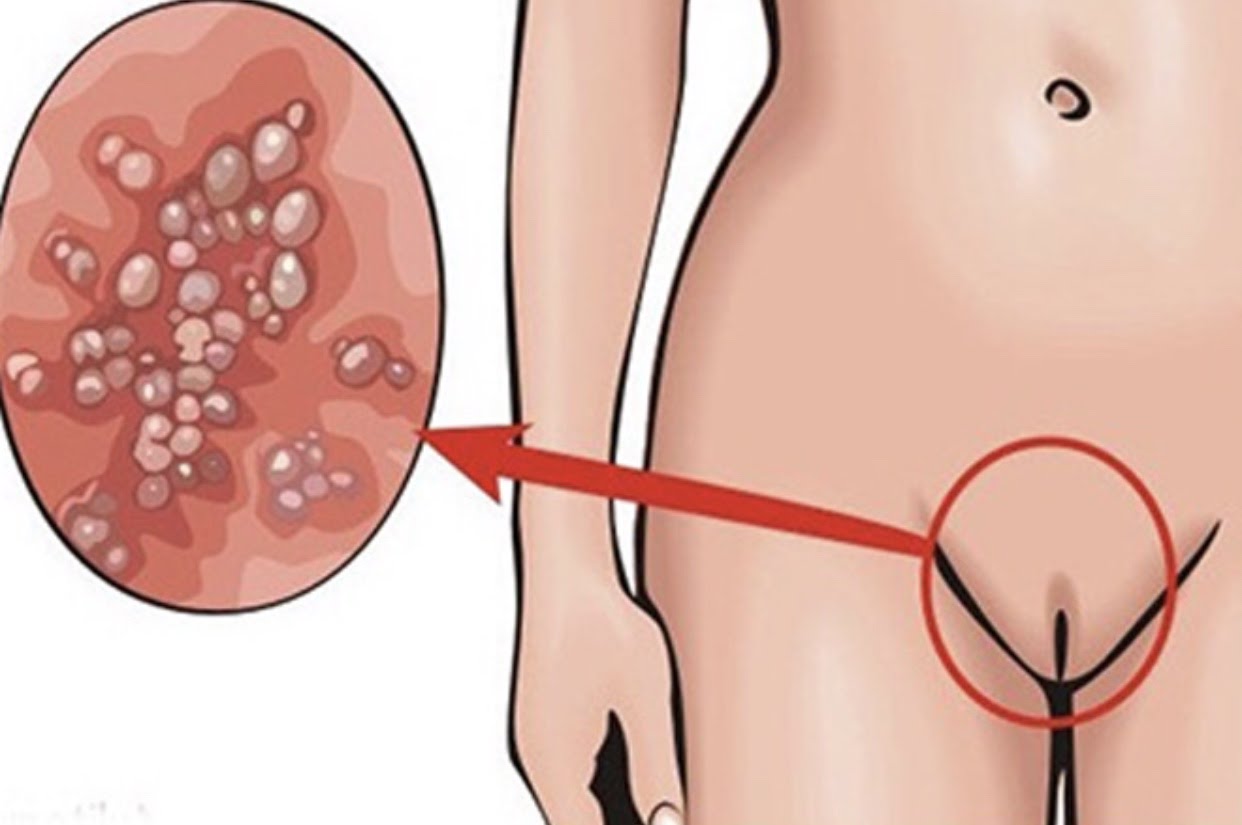

Кондиломы - это одно из самых распространенных заболеваний, передающихся половым путем. Они вызваны вирусом папилломы человека (ВПЧ) и могут появляться на внешних половых органах, анусе, ротовой полости и других областях тела.

Симптомы кондилом могут варьироваться, и визуальное представление этого заболевания может быть различным. Некоторые кондиломы выглядят как небольшие бугорки или бородавки, в то время как другие могут иметь форму плоских пятен или цветных наростов.